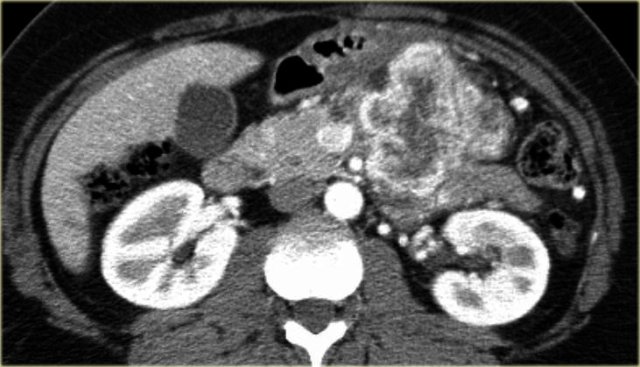

The images show a serous cystic neoplasm (SCN) on a CT.

MRI better shows the central scar.

There are cases when CT can be helpful, since it better depicts a central calcification in SCN or peripheral calcification in a mucinous cystic neoplasm (MCN).

CT images of a mucinous cystic neoplasm with septations and peripheral calcifications.